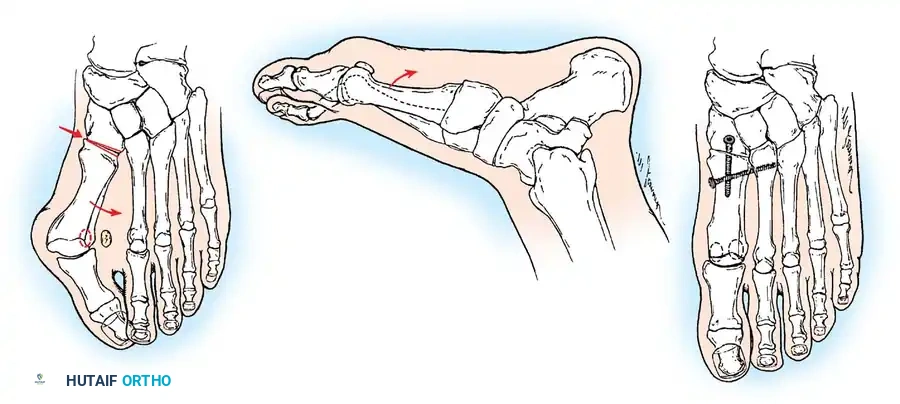

The following modifi cations of the Keller technique can expand the indications for use with more severe deformities.

REMOVAL OF THE FIBULAR SESAMOID

• When the medial eminence and phalangeal base have been excised, remove the fi bular sesamoid.

• Place a sturdy two-toothed retractor beneath the metatarsal head, and have an assistant lift it dorsally.

• Using a Freer elevator or a small osteotome for its strength, mobilize the fi bular sesamoid (Fig. 78-31A to C). This may be diffi cult in elderly patients with signifi cant deformity and adherence of the sesamoid to the metatarsal head. Lift the metatarsal dorsally for exposure (Fig. 78-31D and E).

• When the sesamoid is mobile, identify the fl exor hallucis longus tendon by placing traction on the hallux and fl exing and extending the interphalangeal joint of the hallux. The tendon is visible just distal to and in alignment with the sesamoids, which straddle it.

• Identify and expose the lateral neurovascular bundle just lateral to the tendon by blunt dissection.

• Pull the plantar medial capsule medially. This requires a fi rm grasp on the capsule. The medial traction brings the intersesamoid “ligament” into better view.

• Incise the intersesamoid ligament longitudinally with a No. 67 Beaver or No. 15 Bard-Parker blade. If tenotomy scissors are used, place one arm of the scissors under the ligament (this arm rests on the dorsal side of the fl exor hallucis longus) and the other arm dorsal to the ligament.

• When the intersesamoid ligament is incised, grasp the sesamoid fi rmly with forceps or a small Kocher clamp, fl ex the toe at the interphalangeal and metatarsophalangeal joints to relax the fl exor hallucis longus tendon, and pull the fi bular sesamoid distally and medially.

• With release of the intersesamoid ligament, the medial surface of the fi bular sesamoid is free from soft tissue. Distally, the sesamoid is free because of resection of the base of the proximal phalanx. This leaves two sides of the sesamoid, distal and medial, free of soft tissue.

• While pulling the sesamoid distally and medially, use a small blade to incise along the lateral margin of the sesamoid under direct vision. Keep pulling the head of the metatarsal dorsally and holding the hallux distracted and in fl exion. This greatly aids in identifi cation of the margins of the fi bular sesamoid, particularly laterally and proximally.

• The most diffi cult part of the sesamoidectomy and that which should be done last is release of the proximal lateral corner of the sesamoid where the fl exor hallucis brevis lateral head inserts. While incising the lateral capsular attachments to the sesamoid, do not bury the blade of the knife because the neurovascular bundle to the lateral side of the hallux is just lateral to the capsule.

• Now all attachments to the fi bular sesamoid have been removed except the lateral head of the fl exor hallucis brevis, which inserts on the proximal lateral margin of the sesamoid. This is a diffi cult section to remove; however, this section can be released under direct vision by pulling the sesamoid distally and medially and lifting the metatarsal head dorsally with a strong two-toothed retractor.

LATERAL DISPLACEMENT OF THE FIRST METATARSAL

• Push the metatarsal laterally several times. Occasionally, this does not move the metatarsal, but some lateral mobility usually is present.

Fig. 78-31 Excision of fi bular sesamoid in modifi ed Keller procedure. With base of proximal phalanx removed and medial eminence excision, exposure of fi bular sesamoid is not as diffi cult from medial incision. A, Operative photograph showing elevation of fi rst metatarsal with strong two-tooth retractor and use of small osteotome to mobilize fi bular sesamoid and lateral capsuloligamentous (frequently contracted) structures. Osteotome is between metatarsal head and lateral sesamoid. When mobilization of fi bular sesamoid is complete, entire sesamoid is visible for excision. Note chondromalacia of tibial sesamoid articular surface medial to osteotome. B, Fibular sesamoid has been excised, and lateral capsular structures and conjoined tendon (in forceps) have been released. Neurovascular bundle to lateral side of hallux is adjacent to these structures. C, Diagrammatic representation of modifi ed Keller procedure. By excising fi bular sesamoid, valgus moment of conjoined tendon of fl exor hallucis brevis and adductor hallucis no longer pulls fl exor hallucis longus tendon laterally (carrying hallux with it) through capsulosesamoid plantar plate and pulley system. D, Metatarsal head must be lifted dorsally to excise fi bular sesamoid under direct vision. E, Note exposure of fi bular sesamoid after mobilization of metatarsal head. Continued

Fig. 78-32 Firm fi brous band connects fi bular sesamoid to base of proximal phalanx. Traction on band pulled hallux into valgus. Removing fi bular sesamoid and holding hallux straight for 4 weeks improved results.

Presumably, the laterally displaced fi bular sesamoid, when pulled proximally by the lateral head of the relaxed fl exor hallucis brevis, pulls the fl exor hallucis longus laterally through the sesamoid apparatus, which encases it and contributes to recurrent hallux valgus. In addition, while reoperating after a failed Keller procedure, we observed a strong, linear, fi brous attachment of the fi bular sesamoid to the proximal phalangeal remnant (Fig. 78-32), which pulled the hallux into valgus when tension was applied to it. For these reasons, when the deformity is severe, the hallux and fi rst metatarsal maintain better alignment if excision of the fi bular sesamoid and lateral displacement of the metatarsal are added to the procedure. joint, lateral capsulotomy at the metatarsophalangeal joint, and lengthening of the extensor hallucis longus tendon. Hohmann recommended lateral displacement and plantar tilting of the distal fragment, following osteotomy at the metatarsal neck to correct hallux valgus. In 1945, a report by Mitchell et al. of 100 osteotomies gave the procedure his name. Since then, several authors have presented large retrospective reviews of the Mitchell operation to correct hallux valgus in adults and adolescents, with satisfactory results ranging from 74% to 94%. Gibson and Piggott described a peg-in-hole distal metatarsal osteotomy that differed from the Mitchell procedure in its use of a lateral plantar spike on the proximal fragment in place of the lateral spike on the distal fragment (as recommended by Mitchell). The nonunion rate has been negligible in all series of the Mitchell procedure, and recurrence of the deformity has been infrequent. The most troublesome complication has been metatarsalgia, attributable to dorsifl exion malunion of the distal fragment, excessive shortening of the metatarsal, or both (Fig. 78-33). In a long-term (average 21 years) follow-up study of 105 Mitchell procedures, Fokter, Podobnik, and Vengust found that the most common complication was recurrent hallux valgus with medial eminence pain. Their good-to-excellent results deteriorated from 97% at follow-up ranging from 2 to 11 years to 64% at follow-up ranging from 15 to 24 years, primarily because of recurrence of deformity with medial eminence pain. The use of a Kirschner wire for fi xation (instead of sutures) prevented malunion; all osteotomies healed in 6 weeks with only secondary displacement. Likewise, with the pegin-hole procedure, metatarsalgia has been the most common complication. Relief of pain, narrowing of the forefoot, and correction of the deformity have been achieved in most patients, however. A closing wedge osteotomy at the subcapital level of the fi rst metatarsal to correct valgus of the hallux also has its proponents. Although opponents emphasize that metatarsus primus varus is worsened, and recurrence of the valgus deformity of the great toe is likely, published series have not confi rmed this. Of 32 osteotomies reported by Peabody and 76 reported by Funk and Wells, no nonunions or signifi cant recurrences of the deformity were recorded. A popular osteotomy of the distal metatarsal is the chevron intracapsular osteotomy, which was described by Corless in 1976 as a modifi cation of the Mitchell procedure to correct the bunion associated with mild-to-moderate metatarsus primus varus. The procedure consists of two parts: (1) correction of metatarsus primus varus by a V shaped osteotomy in the sagittal plane through the metatarsal head and neck, followed by lateral shifting of the metatarsal head and trimming of the proximal fragment without internal fi xation (because of the inherent stability of the osteotomy) and (2) correction of the hallux valgus by suturing a previously raised fl ap of joint capsule into the abductor hallucis tendon. Several series of this osteotomy with adequate clinical follow-up have been published. Austin and Leventen reported, in 100 osteotomies randomly selected for analysis from a group of 1200, that no nonunions, osteonecrosis, or infections occurred. Hattrup and Johnson reported, in 225 feet (157 patients), that pain, shoe fi t, and cosmesis were improved in all but a few patients. Because their best results were in younger patients, the authors indicated that